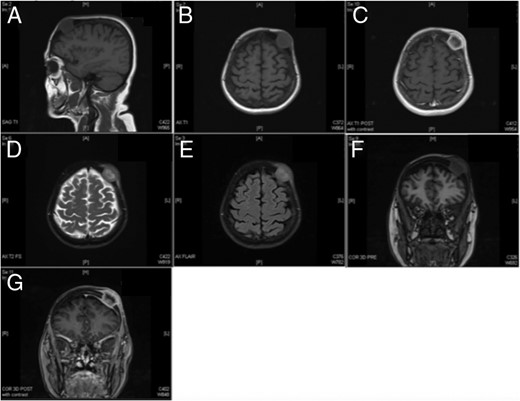

Neurosurgical examination revealed grossly intact cranial nerves with no upper motor neuron signs or motor weakness in all extremities. Sensation was also intact bilaterally. Due to slight effacement of the subarachnoid space and for surgical planning, MRI brain was ordered. MRI demonstrated a 2.8-cm lesion that extended from the subcutaneous fat through the inner and the outer table of the left frontal bone with slight encroachment on the dural space. Minimal mass effect was observed with only slight asymmetry of the fluid signal in the frontoparietal region on the left (Fig. 3). At this time, the decision was made to proceed with a surgical excision. No apparent invasion of the dura or brain parenchyma was noted, thereby satisfying therapeutic and diagnostic aims. The lesion was excised successfully (3.5Â Ă—Â 3.5Â Ă—Â 1.5 cm) with no surgical complications. Histological analysis of the lesion revealed adenocarcinoma that was CK7 positive, CK20 negative and TTF-1 positive. These findings were consistent with a metastatic adenocarcinoma from a lung primary. With stage IV adenocarcinoma, the patient was started on chemotherapy following surgical excision and managed by the oncology service. Her management included a full oncological workup complete with full-body PET scan.

MR imaging redemonstrating the presence of a left frontoparietal mass that does not appear to invade the dura. (A) Sagittal T1, (B) axial T1, (C) axial T1 with contrast, (D) axial T2, (E) axial FLAIR, (F) coronal pre-contrast and (G) coronal post-contrast.